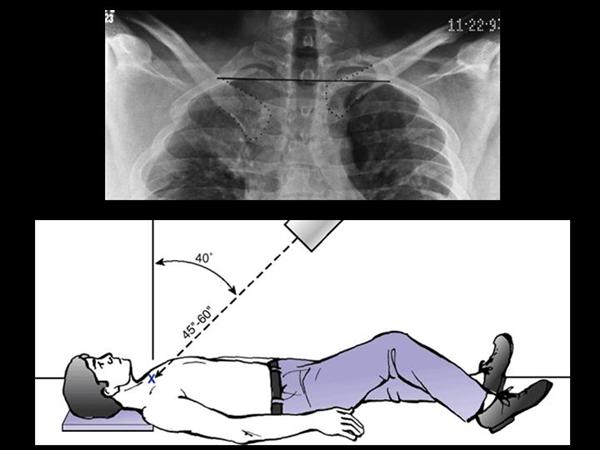

9. Hobbs/Serendipity view : S-C joint D/L